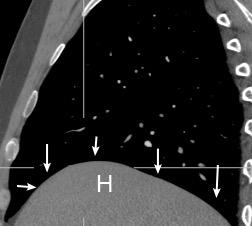

Diafragma “colgante” (“dangling sign”)

(“Dangling sign”)

TC. Mejor con multicorte. (reconstrucciones).

Asociación: Aire en pared.

Fracturas costal .Rotura esplénica. Neumoperitoneo.

Diafragma discontinúo Herniación de la grasa omental

Desser TS et al.The dangling diaphragm sign: sensitivity and comparison with existing CT signs of blunt traumatic diaphragmatic rupture. Emerg Radiol 2010